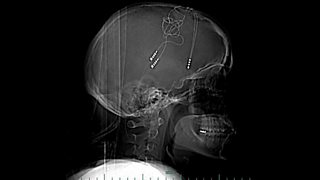

When all the other treatments failed to help her depression Brandy turned to technology.